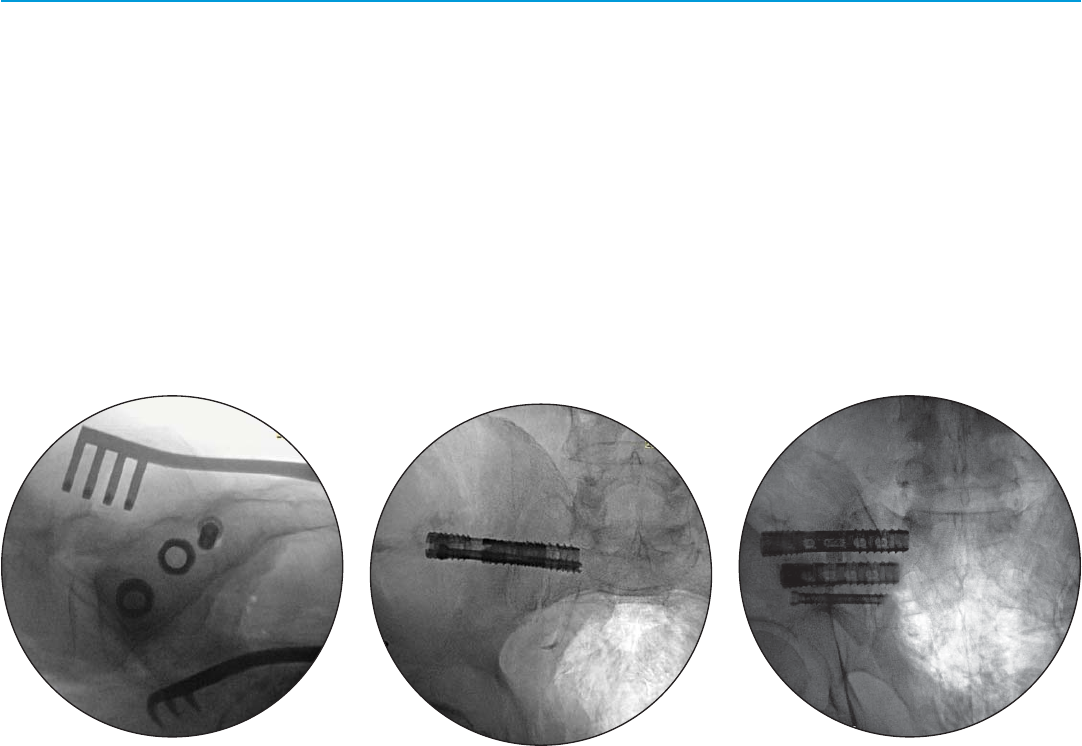

Step 12

Outlet View

Implant progression. Initial placement.

(Fig. 12a)

Implant progression.

(Fig. 12b)

Implant progression. Fully seated.

(Fig. 12c)